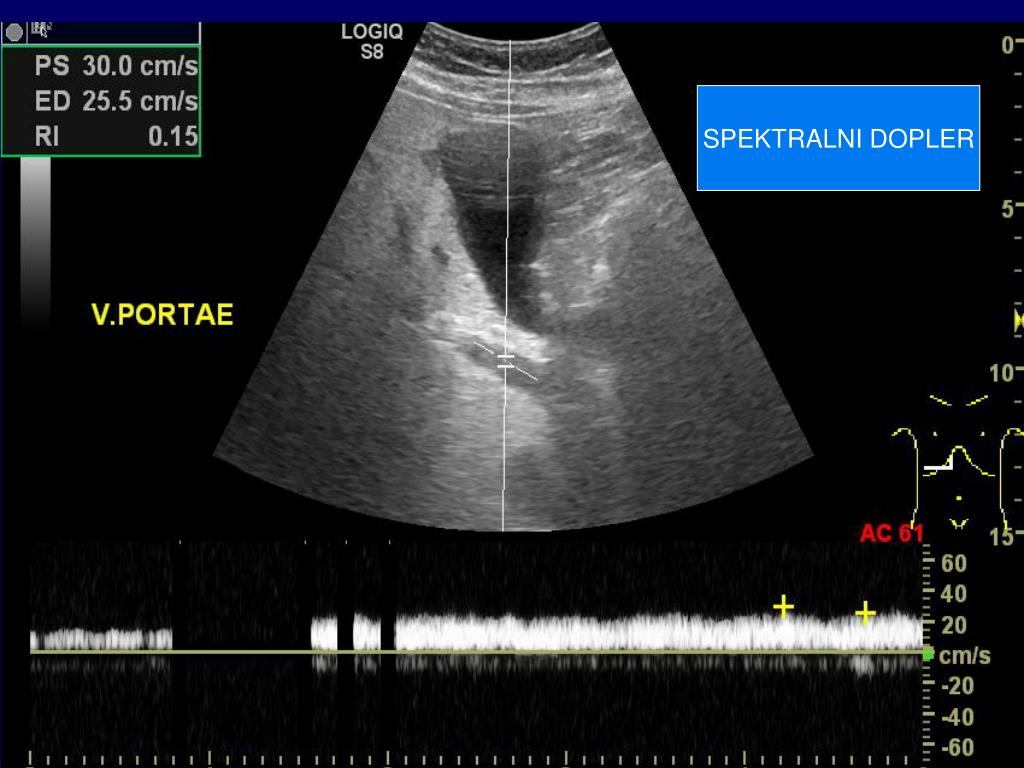

19. SPEKTRALNI DOPLER

20. SPEKTRALNI DOPLER